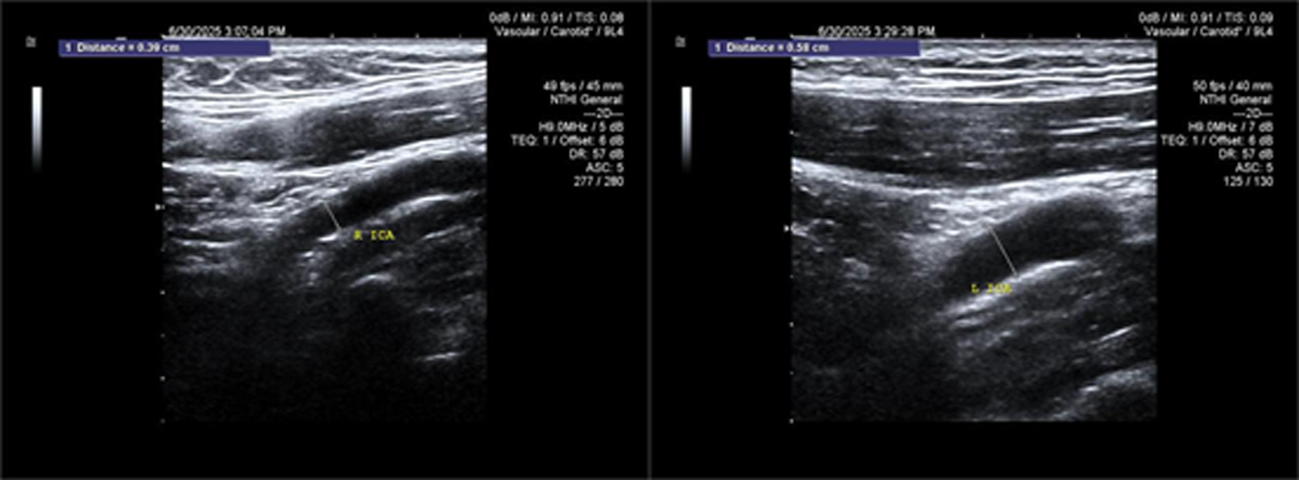

Objective To summarize diagnostic and differentialdiagnostic approaches for initial detection of moyamoya disease (MMD) using carotid ultrasound (CAU). Methods We report two patients who were first diagnosed with MMD by CAU and summarize the diagnostic reasoning and differential considerations. Relevant literature was reviewed to contextualize these findings. Results Case 1: A 57-year-old female presented with a >10 year history of dizziness and headache with recurrence over 3 days. CAU showed a reduced diameter of the left internal carotid artery (ICA), decreased flow velocity, and a lower resistance index, raising suspicion for severe intracranial stenosis or occlusion and prompting clinical exclusion of MMD. Magnetic resonance angiography (MRA) confirmed severe stenosis of the left ICA with absent distal branches and multiple small abnormal vascular networks in the left suprasellar region, consistent with MMD. Case 2: A 23-year-old male presented with dizziness for >1 year and transient right upperlimb weakness for 1 day. CAU and transcranial color Doppler (TCCD) showed a narrowed right ICA with reduced flow velocity and increased resistance index, suggesting chronic occlusion of the right middle cerebral artery and stenosis of the left middle cerebral artery, raising the possibility of MMD. MRA demonstrated an indistinct right ICA and right middle cerebral artery and narrowing of the left middle cerebral artery. On followup, the patient was diagnosed with MMD. Conclusion When CAU reveals a small internal carotid artery diameter accompanied by slowed flow velocity, clinicians should perform a comprehensive evaluation-including TCCD and further vascular imaging-to avoid missed or incorrect diagnoses of MMD.